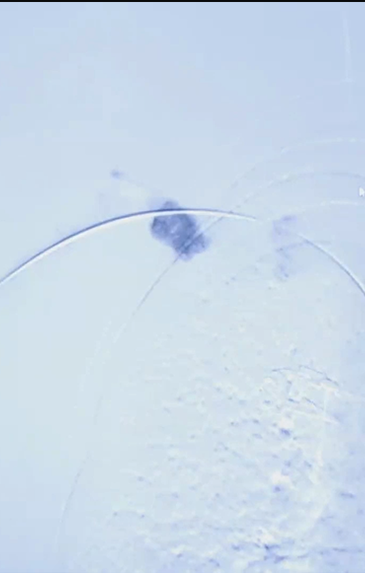

4/ 造影示头静脉弓破裂,遂植入7mm×59mm VBX(GORE)球扩覆膜支架;

5/ 多角度造影评估支架位置及形态,触摸吻合口震颤良好,缝合穿刺点,术毕。

右上肢透析静脉血流量恢复正常,静脉压恢复正常,右肱动脉血流达1198ml/min。